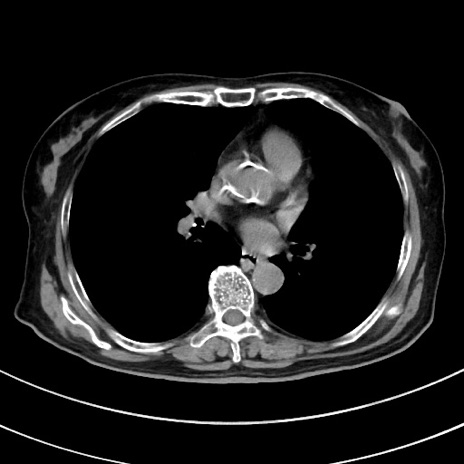

冠状断像